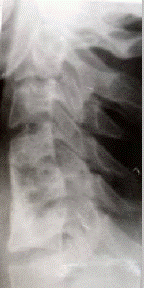

Г.М. Кавалерский, В.Г. Германов, В.К. Никурадзе, А.Н. Каранадзе,К.В. Сотиков, А. УмаровМосковская медицинская академия им. И.М. Сеченова,Городская клиническая больница № 7 г. Москвы,2-й Ташкентский медицинский институт ИСПОЛЬЗОВАНИЕ ИСКУССТВЕННЫХ БИОКОМПОЗИЦИОННЫХ МАТЕРИАЛОВ В ХИРУРГИЧЕСКОМ ЛЕЧЕНИИ ПОВРЕЖДЕНИЙИ ЗАБОЛЕВАНИЙ ПОЗВОНОЧНИКАРЕФЕРАТ До последнего времени основным пластическим материалом для замещения костных дефектов и стимуляции остеогенеза в травматологии-ортопедии и, в частности, для формирования костного блока в хирургии позвоночника, остаются ауто- или аллокость. Однако, традиционная костная пластика, применяемая при операциях стабилизации позвоночника не всегда позволяет добиться образования костного блока оперированных позвоночных сегментов. Перспективным пластическим материалом является КоллапАн фирмы “Интермедапатит”. Обладая выраженными остеогенными свойствами и являясь матрицей для образования костной ткани, КоллапАн создает условия для улучшения репаративных процессов в костной ране. Авторами описывается обобщенный опыт использования КоллапАна при операциях на позвоночнике, особенности и сроки формирования костного блока на основе КоллапАна при стабилизации позвоночника углеродными имплантатами и пластинами Каплана-Вильсона. Лечение повреждений и заболеваний позвоночника остаётся одной из актуальных проблем травматологии-ортопедии. Оперативного лечения требуют многие заболевания и повреждения позвоночника (дегенеративно-дистрофические процессы, опухоли, осложненные и нестабильные переломы позвонков и т.д.). Основными этапами операции, как правило, являются освобождение компремированных структур позвоночного канала (при необходимости) и стабилизация оперированных сегментов с целью создания условий для формирования костного блока. Существует большое разнообразие вариантов спондилодеза, отличающихся доступом и используемыми конструкциями. Однако, ни один из них не учитывает или активно не влияет на репаративный потенциал костной раны. В связи с этим в послеоперационном периоде требуется иммобилизация (иногда довольно длительная) позвоночника до образования костного блока оперированных позвоночных сегментов. В настоящее время всё же существуют конструкции для фиксации позвоночных сегментов при спондилодезе, позволяющие освободить пациентов от длительной иммобилизации позвоночника. Среди последних одними из наиболее надежных считаются пластины и транспедикулярные системы различных зарубежных производителей. Однако, дорогая стоимость существенно ограничивает возможности их повсеместного использования. В качестве пластического материала при спондилодезе традиционно чаще всего используются алло- или аутокость [8,11,12]. Отрицательными моментами аллопластики являются вопросы, связанные с заготовкой, хранением костной ткани и заболеваниями, передающимися через различные среды организма (СПИД, гепатит С и т.д.); а также влиянием различных консервантов на биологические свойства трансплантата [8]. В ряде стран по религиозным соображениям вообще запрещена какая-либо трансплантация органов и тканей. Главными недостатками пластики аутокостью является необходимость дополнительной операции и ограниченные размеры получаемого трансплантата. Обширные резекции тел позвонков или стабилизация позвоночника на 2-х и более уровнях в значительной степени снижают репаративные свойства костного ложа. При этом может наблюдаться лизис трансплантатов, формирование фиброзного блока или нестабильности. Описаны также случаи миграции трансплантата [8,9,12]. В связи с этим продолжается поиск и создание искусственных материалов, способных заменить костную ткань и сводящих к минимуму недостатки костной алло- и аутопластики. Перспективным остеопластическим материалом является КоллапАн фирмы “Интермедапатит”. КоллапАн относится к биокомпозиционным материалам нового поколения, cозданных на основе искусственного гидроксиапатита (ГАП) и коллагена [1-7,9,10]. Компонентами материала являются искусственный ГАП (химическая формула Ca5 (PO4 )3 OH), коллаген и антибиотик. Имеется широкий выбор антибиотиков, однако, по желанию заказчика препарат может быть предоставлен без них. Гидроксильные и фосфатные ионы (см. формулу) могут частично замещаться карбонатом. Это по составу приближает данный ГАП к биологическому. Молярное отношение Ca/P – 1,67 (в костях человека 1,37 – 1,77). Ультрадисперсный порошок гидроксиапатита равномерно распределен в матрице из особо чистого коллагена второго типа и антибиотика. Антибиотик и микрокристаллы гидроксиапатита постепенно высвобождаются из коллагеновой матрицы при ее лизисе и разлагаются путем химических превращений до ионов Ca и P, входя затем в структуру костного регенерата. На частицах растворяющегося искусственного гидроксиапатита путем эпитаксиального роста осаждается биологический ГАП, составляющий минеральную основу будущей костной ткани. Формируется остеоидный матрикс, постепенно созревающий и превращающийся в зрелую пластинчатую кость, в которой определяются остатки резорбируемого гидроксиапатита [1 - 4, 10]. Таким образом, формирование новой кости начинается непосредственно на КоллапАне. Фиброзная прослойка между КоллапАном и новообразующейся костью при этом не определяется. Из сказанного следует, что КоллапАн обладает остеокондуктивностью, а присутствие в его составе коллагена и антибиотиков придает ему противовоспалительные, антимикробные и остеоиндуктивные свойства. Поставляется КоллапАн в готовых к применению стерильных упаковках. Каждая упаковка гранул КоллапАна имеет строго определенное количество вещества, рассчитанное на заполнение определенного объема костной полости или дефекта костного вещества. С целью активного воздействия на остеогенез мы модернизировали технику стабилизации позвоночника традиционными и доступными широкому кругу пациентов фиксаторами (углеродными имплантатами и пластинами Каплана-Вильсона), используя в качестве пластического материала для формирования костного блока и улучшения репаративных возможностей костной раны остеогенный препарат КоллапАн. Группу наблюдения составили 150 пациентов с заболеваниями и повреждениями шейного отдела позвоночника и 45 пациентов с повреждениями нижнего грудного и поясничного отделов позвоночника. Показаниями к оперативному лечению в шейном отделе позвоночника являлись: 1) нестабильные повреждения в остром и отдаленном периоде (подвывихи, вывихи, переломо-вывихи, переломы тел позвонков) - 118 пациентов; 2) оссификация задней продольной связки - 23 пациента; 3) метастатические поражения тел позвонков - 9 пациентов. Среди больных с травмой преобладали лица мужского пола в возрасте от 15 до 32 лет. В группе больных с оссификацией задней продольной связки (болезнью Цукимото) наблюдались только мужчины. Возраст от 38 до 59 лет. В группе больных с метастатическими опухолями в шейном отделе позвоночника были только женщины. Возраст от 48 и 59 лет. У каждого больного в данной группе можно было выделить несколько синдромов, сочетание которых и преобладание отдельных при каждой нозологии имели свою особенность, что затруднительно выразить в табличной форме. Однако, главными синдромами, встречающимися в группе пациентов с заболеваниями и повреждениями шейного отдела позвоночника, мы сочли болевой (127 пациентов), корешковый (85 пациентов), миелорадикулопатии (25 пациентов). В нижнем грудном и поясничном отделах позвоночника показаниями к оперативному лечению являлись нестабильные переломы тел позвонков. Возраст пациентов составил от 17 до 52 лет. В клинической картине наблюдались болевой (39 пациентов) и корешковый (6 пациентов) синдромы. Последний в наших наблюдениях встретился у больных с взрывным переломом тела L4 позвонка и имел ишиалгический характер боли. Оперативное лечение повреждений и заболеваний в шейном отделе позвоночника выполнялось из переднего доступа. Этапы операции включали продольное рассечение передней продольной связки, резекцию поврежденных структур (диска, тел позвонков, задней продольной связки) с целью декомпрессии, вправление вывиха (если необходимо), стабилизацию оперированных сегментов углеродным имплантатом, фиксированным в телах смежных с ним позвонков костным цементом. На углеродный имплантат укладывались гранулы КоллапАна в количестве, достаточном для заполнения остаточного дефекта и над ними ушивалась передняя продольная связка. Операция заканчивалась дренированием заглоточного пространства и послойным швом раны. При нестабильных повреждениях в грудо-поясничном и поясничном отделах позвоночника выполнялась следующая техника оперативного вмешательства. Под наркозом на ортопедическом столе осуществляли репозицию поврежденных позвонков. Задним доступом осуществляли подход к остистым отросткам и дужкам тел позвонков. Выполняли стабилизацию поврежденного сегмента пластиной Вильсона-Каплана по общепринятой методике. После этого в тело разрушенного позвонка пункционно вводили КоллапАн гель в количестве 4 – 5 мл. Количество вводимого препарата контролировали ощущением эластического сопротивления поршня шприца. Затем рану дренировали и послойно ушивали. Дренирование околопозвоночного пространства проводили в режиме отсасывания. К активизации больных приступали через 1 – 2 дня после операции по удалении дренажа. Активизацию осуществляли с иммобилизацией шейного отдела позвоночника съемным воротником Шанца. Сроки ношения воротника зависели от объема операции и определялись достижением костного блока на уровне оперированных сегментов. Активизацию больных после металлоспондилодеза пластинами Каплана-Вильсона проводили без иммобилизации позвоночника. Использование предложенной технологии спондилодеза не выявило особенностей клинического течения ближайшего и раннего послеоперационных периодов в сравнении с известными методиками. Купирование боли и регресс неврологических симптомов проходил в обычные сроки. В одном наблюдении, однако, у больного с оссификацией задней продольной связки сохранилась симптоматика миелорадикулопатии. В данном случае длительность заболевания была более 2 лет. Больной был инвалидом II группы. В то же время в послеоперационном периоде прогрессирования заболевания не отмечено. Контроль формирования костного блока на уровне оперированных позвоночных сегментов в ближайшем и отдаленном послеоперационных периодах с использованием рентгенологических методов (включая функциональные), КТ и компьютерной денситометрии показал следующее. Сроки формирования костного блока зависели от объема резекции, а не от характера патологического процесса и его локализации. Так при спондилодезе на одном уровне блок сформировался в среднем за 7 недель (7,1+_0,2). На двух уровнях – за 9 недель (9,3+_0,3). На трех уровнях – за 12 (12,3+_0,1) недель. В качестве иллюстрации приводим рентгенологическую картину формирования костного блока у больного В., 21 лет, которому выполнен спондилодез на двух уровнях по поводу нестабильного перелома С6 позвонка (см. рисунок 1).

а) б) в) Рис.1. Больной В., 21 лет. Д–з: нестабильный перелом тела С6 позвонка. а – при поступлении; б – 7 дней после операции; в – 11 недель после операции. Существенных различий по средним срокам формирования костного блока в зависимости от уровня оперированных сегментов в наших наблюдениях не выявлено. Приблизительно в одинаковые сроки сформирован блок на уровне и высоко мобильных, и мало мобильных сегментов. Это касается как спондилодеза на одном сегменте, так и на двух сегментах. Функциональное рентгенографическое исследование, выполненное у больных по завершении формирования костного анкилоза, показало отсутствие подвижности на уровне оперированных сегментов. Данные рентгенографического исследования подтверждались компьютерной денситометрией. Средние показатели плотности формирующегося костного блока в единицах Хаусфилда нарастали постепенно, сравниваясь с плотностью прилежащих тел позвонков к моменту рентгенографической картины сформированного костного блока. В грудо-поясничном и поясничном отделах позвоночника использование Отдаленные результаты наблюдения за пациентами с повреждениями и заболеваниями шейного отдела позвоночника показали, что во всех наблюдениях в процессе формирования костного блока сохранилась достигнутая во время операции коррекция статики позвоночника. Признаков рассасывания костного блока не зарегистрировано. При этом больные вели активный образ жизни с сохранением двигательной нагрузки на шейный отдел позвоночника. После формирования костного блока трудоспособность у всех пациентов восстановлена, кроме пациента с болезнью Цукимото, имевшего инвалидность II группы еще до оперативного лечения и пациентов с метастазами в тела позвонков. У последних, однако, улучшилось качество жизни. Таким образом, полученные результаты оперативного лечения повреждений и заболеваний позвоночника указывают на целесообразность использования КоллапАна для оптимизации репаративных процессов в костной ране при операциях спондилодеза. При умеренных дефектах в шейном отделе позвоночника предлагаемая технология позволяет исключить костную аутопластику, что позволяет снизить травматичность оперативного вмешательства и исключает отрицательные моменты аллопластики. Использование КоллапАна для улучшения репаративного потенциала костной раны при спондилодезе пластинами Вильсона-Каплана является мерой профилактики вторичной компрессии тел позвонков в результате такого типичного осложнения, как развинчивание винтов конструкции. К моменту спонтанного развинчивания (если оно появляется) прочность тел позвонков уже восстановлена. Последующее нарушение прочности металлоконструкции в результате не вызывает вторичной компрессии тел позвонков. СПИСОК ЛИТЕРАТУРЫ 1. Басченко Ю.В. Физико-химические свойства нового биокомпозиционного материала для костной пластики “Коллапан”. // Докл. Науч.-практ. конф. “Применение “Коллапана” в травматологии и хирургии”. – Москва, ЦИТО им. Н.Н. Приорова, 3 октября 1996г. 2. Берченко Г.Н., Бурдыгин В.Н., Уразгильдеев З.И., Кесян Г.А., Басченко Ю.В., Макунин В.И., Бушуев О.М. Патоморфологическое обоснование использования материалов на основе гидроксиапатита для замещения дефектов костной ткани. // В кн.: Удлинение конечностей и замещение дефектов костей. – Республика Крым, Ялта, 1996 – С. 11-12. 3. Берченко Г.Н., Уразгильдеев З.И., Кесян Г.А., Макунин В.И., Бушуев О.М. Активизация репаративного остеогенеза с помощью биоактивных резорбируемых материалов - кальций фосфатной биокерамики и комплексного препарата КоллапАн. // Ортопедия, травматология и протезирование. Харьков.- 2000-№2 – С. 96. 4. Берченко Г.Н., Уразгильдеев З.И., Бурдыгин В.Н., Кесян Г.А., Макунин В.Н., Бушуев О.М. Использование аллопластических материалов на основе гидроксиапатита в качестве матрицы для формирования костной ткани. // В кн.: Биокомпозиционные материалы в челюстно-лицевой хирургии и стоматологии. Тезисы докладов 1 Всероссийской научной конференции. Москва, 20-21 ноября 1997г. – М.: МОНИКИ, 1997. – С.14. 5. Германов В.Г. Применение КоллапАна при стабилизирующих операциях на шейном отделе позвоночника: Автореф. дисс... канд. мед. наук. – М., 1999. – 21с. 6. Кавалерский Г.М., Германов В.Г., Гордеев Г.Г., Рабинович Л.С., Семенов А.Ю. Особенности остеогенных процессов в присутствие КоллапАна при лечении нарушений консолидации переломов длинных костей. // В кн.: Актуальные вопросы лучевой диагностики в травматологии, ортопедии и смежных дисциплинах. Тез. докл. науч.- практ. конфер. РНЦ ВТО им. Акад. Г.А. Илизарова. Курган, 2-3 октября 2003 г.- С. 207-209. 7. Кавалерский Г.М., Германов В.Г., Невзоров В.А., Козлов Д.Н., Каранадзе 8. Корж Н.А., Пульбере О.П., Михайлов С.Р., Чертенкова Э.В. О потере коррекции деформации шейного отдела позвоночника после межтелового спондилодеза. // Ортопедия, травмат. – 1990 - № 11 – С. 17-21. 9. Проценко А.И., Германов В.Г., Бережной С.Ю., Сотиков К.В., Горина Л.Б. Применение КоллапАна при стабилизации позвоночника после расширенной резекции тел позвонков. // Вестник травматологии и ортопедии им. Н.Н. Приорова. –1999 -№3- С. 49-52. 10. Шапошников Ю.Г., Кесян Г.А., Берченко Г.Н. Комплексное лечение огнестрельных переломов с использованием препарата “Коллапан”. // В кн.: Актуальные вопросы клинич. медицины. – М., 1996 - С. 41. 11. Юмашев Г.С., Фурман М.Е. Остеохондрозы позвоночника. – М.: Медицина, 1984. – 384с. 12. Cloward R.B. Complications of anterior Cervical Disc Operation and their Treatment. // Surgery. – 1971. –v. 69. - № 3. – P. 175-172. |